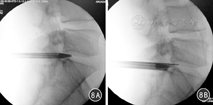

后路经椎板间孔入路首选于L5/S1腋部、肩部及游离型椎间盘突出。对于髂嵴较高、横突较大及椎间孔狭窄的患者,首选椎板间隙入路摘除椎间盘。穿刺进针点的X线透视侧位位于S1椎体后缘或椎间隙内(图8),正位位于术侧椎弓根上缘连线内侧缘,即后纵韧带边缘。穿刺完成后建立工作通道并摘除椎间盘。